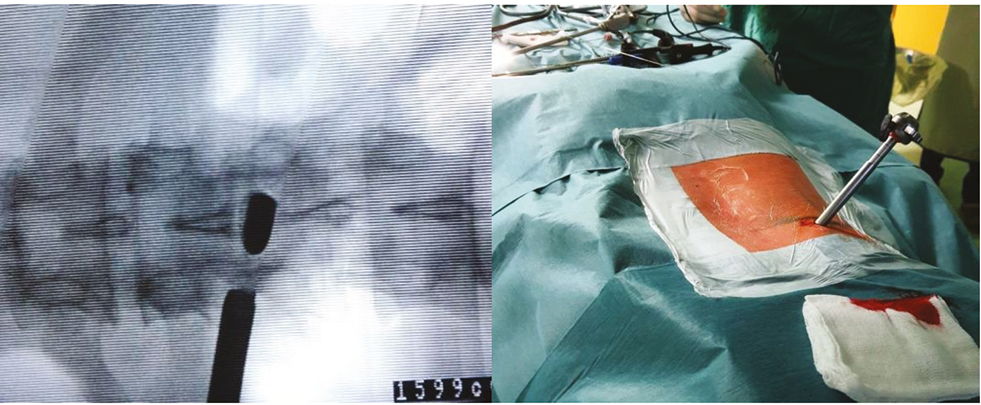

Под общей многокомпонентной анестезией с интубацией трахеи в положении больного на животе под рентгенологическим контролем в прямой и боковой проекциях в нижнюю часть левого межпозвонкового отверстия LI–LII последовательно установлены игла 18G и проводник. Игла удалена. В месте пункции выполнен разрез кожи и мягких тканей длиной 1 см. По проводнику установлен конусообразный направитель. Под рентген-контролем по конусообразному направителю последовательно установлена рабочая трубка. После рентген-контроля в двух проекциях направитель, проводник и направляющие трубки удалены (рис. 3).

Рис. 3. Этап эндоскопического трансфораминального доступа к инородному телу поясничного отдела позвоночника

Fig. 3. Stage of endoscopic transforaminal access to a foreign body of the lumbar spine